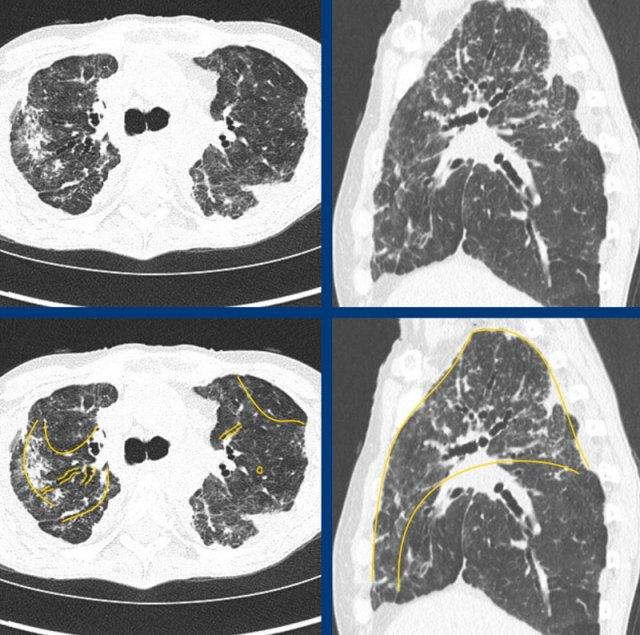

Xơ hóa trong bệnh sarcoidosis thường có biểu hiện ưu thế ở vùng quanh phế quản mạch máu và vùng phổi giữa đến trên với biến dạng cấu trúc và giãn phế quản do co kéo trung tâm, kèm theo một lượng thay đổi của dạng lưới và đôi khi thậm chí có tổ ong.

Các

hình ảnh cho thấy bệnh sarcoidosis xơ hóa điển hình với tổn thương ưu thế quanh phế quản-mạch máu và vùng đỉnh, biểu hiện dạng nốt (hợp lưu), lưới và kính mờ nhẹ, cùng với giãn phế quản do co kéo lan rộng.